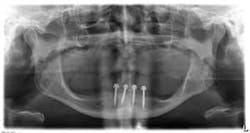

A more positive point of view, which was recently articulated to me by my colleague, Dr. Alvaro Ordonez, from Miami, was that the total professionalism of one's office as well as its commitment to current technological advances, such as CT implant planning and CT-assisted implant placement, are significant factors when presenting treatment alternatives that have very different prices (e.g., small diameter implants to provide increased denture stability and retention versus “four on the floor“ with a milled connector bar and a new over-denture prosthesis).